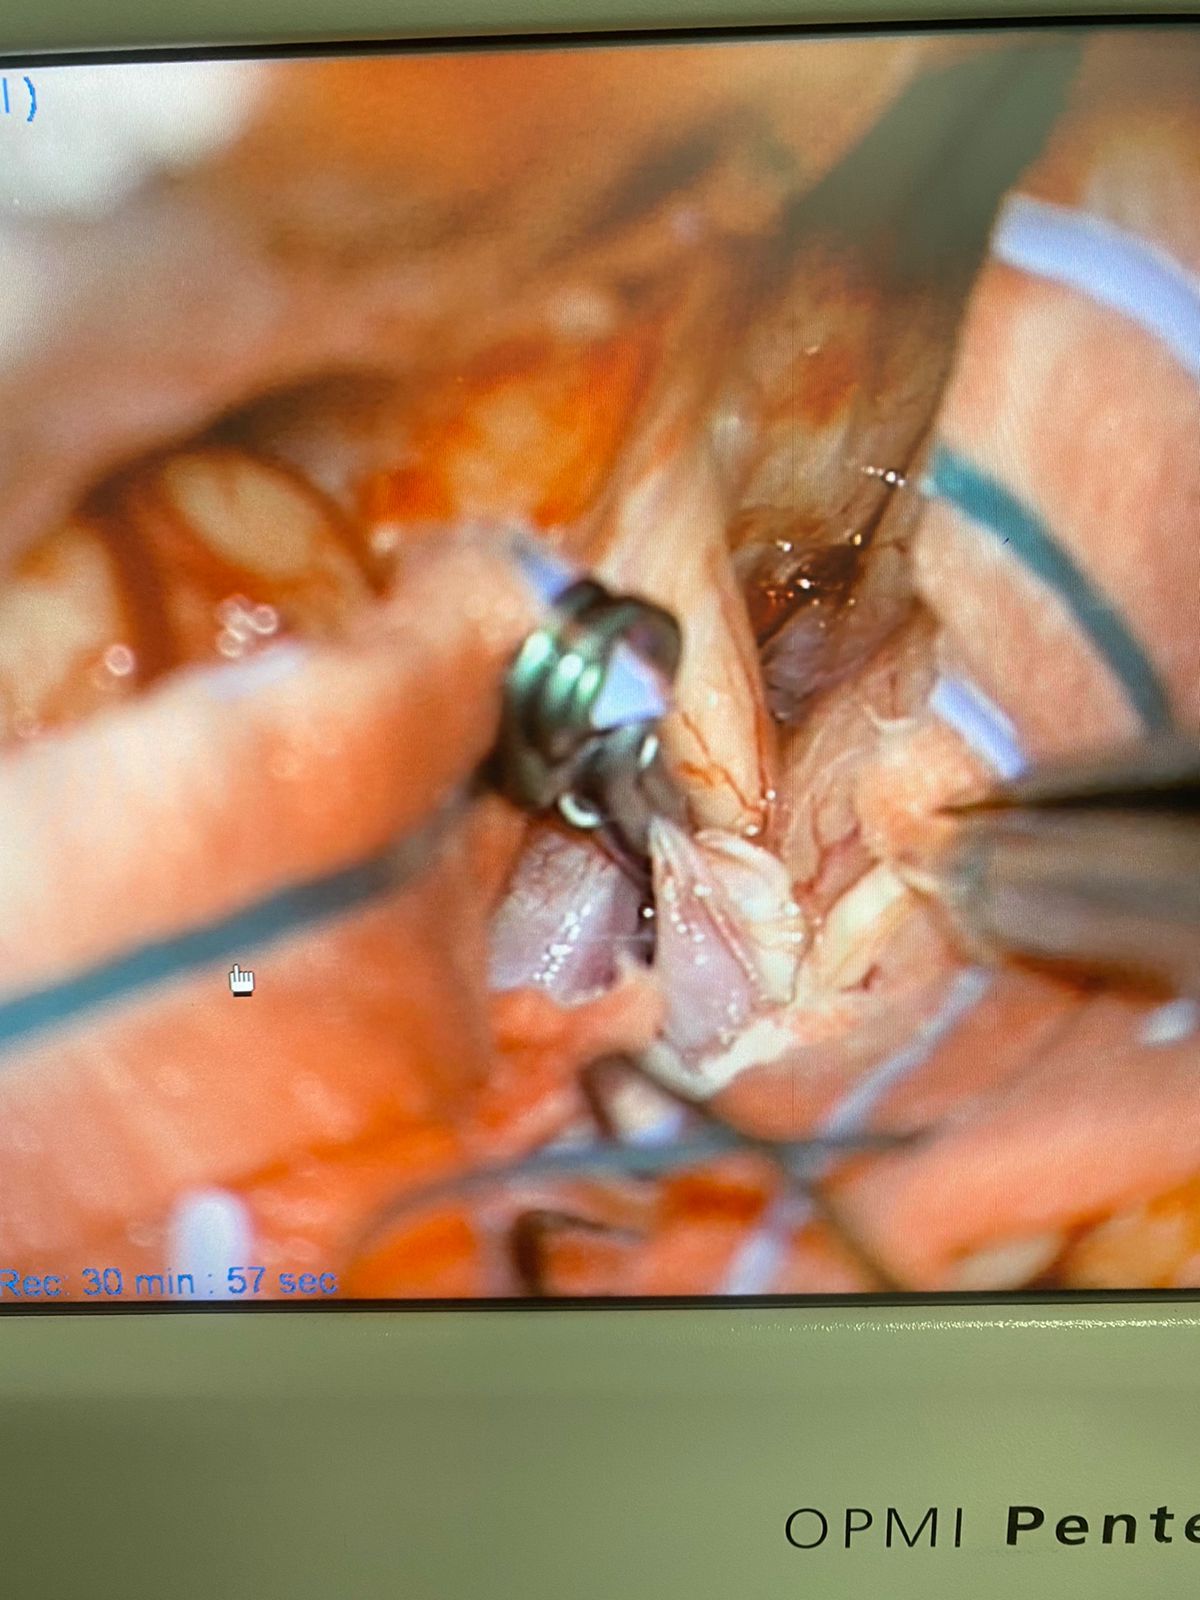

Mis principales áreas de interés dentro de la neurocirugía son los tumores del sistema nervioso, columna y neuro trauma, aplicando técnicas modernas como microcirugía, mínima invasión y endoscopía.

My main areas of interest are nervous system tumours, spinal surgery, and neuro trauma, applying modern techiques as microsurgery, minimal invasive surgery and endoscopy assistance.